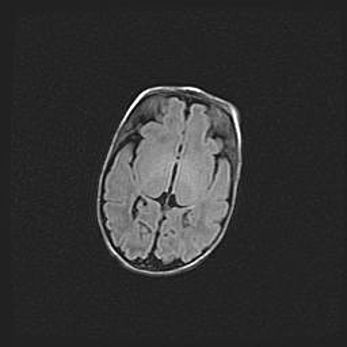

Сообщающаяся гидроцефалия. Кистозная энцефаломаляция головного мозга.

Возраст: 3 месяца 4 дня

Вес: 3100 г

Пол: женский

Окружность головы: 34 см

Срок гестации: 31 неделя

Кистозная энцефаломаляция головного мозга - одна из форм поражения головного мозга в детском возрасте. Характеризуется возникновением множественных и распространённых кист в коре, белом веществе и подкорковых образованиях головного мозга у плодов, новорождённых и детей раннего возраста. Развитие кистозной энцефаломаляции связано с внутриутробной асфиксией и гипотонией, родовой травмой, тромбозом синусов, пороками развития сосудов, инфекциями, сепсисом и другими причинами. Наиболее значимые инфекционные агенты: вирусы простого герпеса, цитомегалии, краснухи, токсоплазмы, энтеробактерии, золотистый стафилококк и другие.